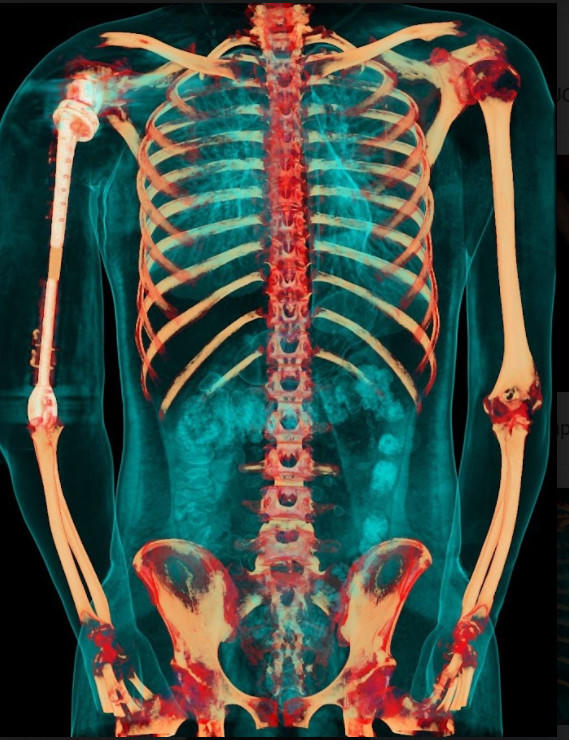

Nhóm phẫu thuật đã lên kế hoạch sử dụng các công nghệ trong tái tạo xương hiện đại nhất hiện nay bao gồm tái tạo lại cấu trúc khớp vai, cấu trúc khớp khuỷu bằng vật liệu hợp kim titan. Đặc biệt, đội ngũ bác sĩ của Trung tâm đã có một quyết định định táo bạo: không sử dụng hoàn toàn vật liệu kim loại mà chế tạo phần thân xương cánh tay sử dụng công nghệ in 3D vật liệu polyme sinh học (PEEK). Vật liệu này do phòng nghiên cứu ứng dụng công nghệ in 3D của Đại học VinUni sản xuất, giúp kết nối phần khớp vai và khớp khuỷu với nhau, đồng thời phục hồi lại điểm bám của các gân cơ quanh cánh tay. Đây được coi là một quyết định đầy tính sáng tạo dựa trên những nghiên cứu và thử nghiệm chuyên sâu từ nhiều ca bệnh đã thành công của ê-kíp phẫu thuật.

Đặc biệt, công nghệ in 3D được coi là công nghệ duy nhất hiện nay mang lại khả năng cá thể hóa các chi tiết cấy ghép. Nhờ công nghệ này, cả 3 phần của xương cánh tay nhân tạo đều được “thiết kế riêng” theo đúng kích thước cánh tay thật của bệnh nhân, đồng thời có các điểm cố định giúp khôi phục lại hệ thống gân cơ bám xương. Trước khi sản xuất, tất cả những thiết kế này đều được thử nghiệm mô phỏng khả năng vận động, chịu lực trên máy tính. Nhờ vậy, xương nhân tạo sau ghép sẽ tương thích tối đa, “hoàn toàn vừa vặn” với cơ thể người bệnh và thời gian phục hồi chức năng vận động của cánh tay sẽ được rút ngắn đáng kể.

Ca phẫu thuật phục hồi cánh tay cho bệnh nhân V.T.Đ là ca bệnh đầu tiên trên thế giới sử dụng kết hợp vật liệu giữa hợp kim titan và vật liệu y sinh PEEK do các bác sỹ của Trung tâm CTCH&YHTT Vinmec thực hiện

Việc sử dụng kết hợp 2 loại vật liệu trên cùng một xương nhân tạo để tận dụng được ưu điểm tối đa: tính vận động chính xác, linh hoạt của hợp kim titanium tại vùng khớp, và đặc tính nhẹ, bền, tương thích với cơ thể của vật liệu PEEK. Nhờ vậy, trọng lượng cánh tay nhân tạo có thể giảm xuống còn 1 nửa và chi phí giảm tới hơn 1/3 so với việc chỉ dùng vật liệu kim loại như trước đây.